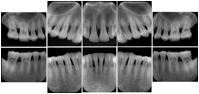

Intra-oral radiography typically involves acquisition of multiple images of various parts of the dentition. Many digital radiographic systems offer customized templates that are used for displaying the images in a study on the screen. These templates may also be referred to as mounts or view sets. The Structured Display Object represents a standard method of encoding and exchanging the layout and intended display of Structured Displays. A structured display object created in this manner could be stored with a study and exchanged with images to allow for complete reproduction of the original exam.

1. A patient visits a General Dentist where a Full Mouth Series Exam with 18 images is acquired. The dentist observes severe bone loss and refers the patient to a Periodontist. The 18 images from the Full Mouth Series along with a Structured Display are copied to a DICOM Interchange CD and sent with the patient to see the specialist. The Periodontist uses the CD to open the exam in his Dental Radiographic Software and consults via phone with the General Dentist. Both are able to observe the same exam showing the images on each user's display using the exact same layout.

Intra-oral Full Mouth Series Structured Display

Figure OO-1. Intra-oral Full Mouth Series Structured Display